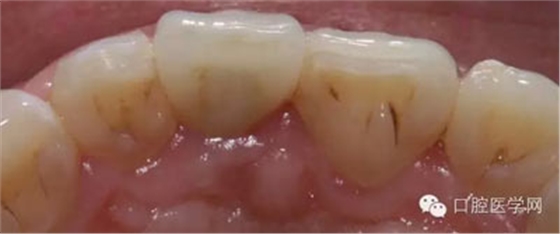

7、術(shù)后照飽和度調(diào)到最低與最高,觀察牙齒修復(fù)后的明度及飽和度

8、術(shù)前術(shù)后對(duì)比